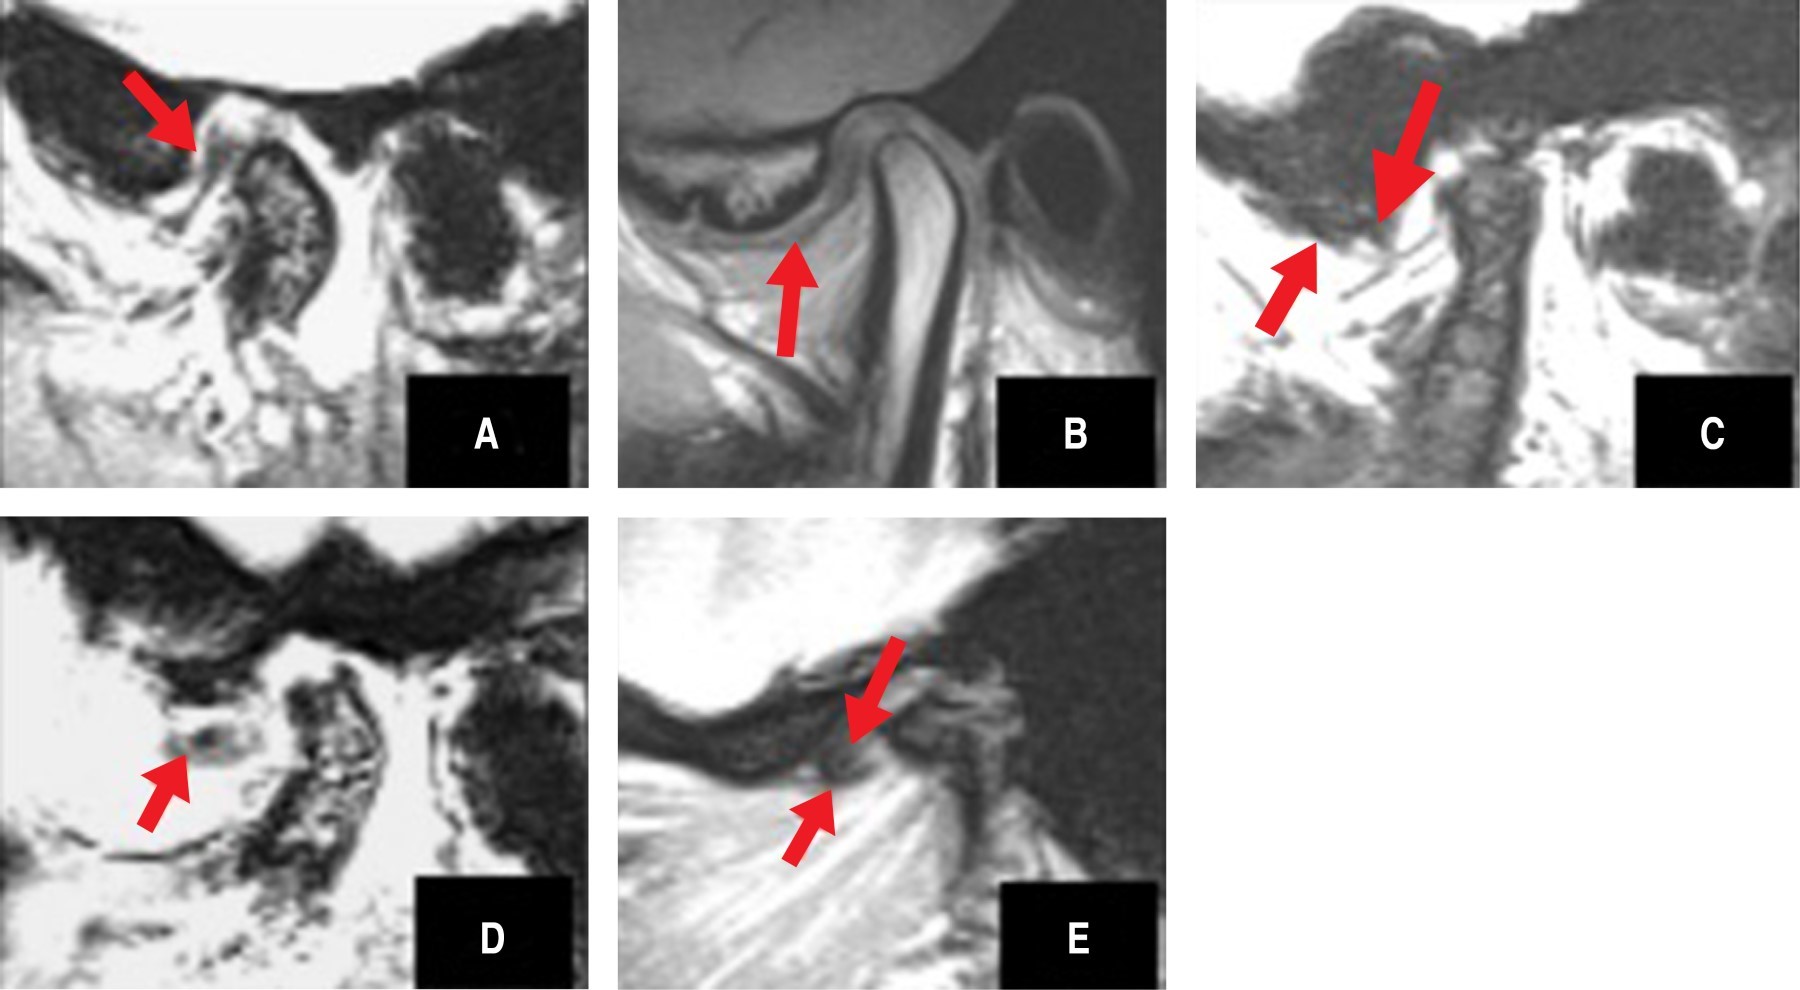

Figure 4